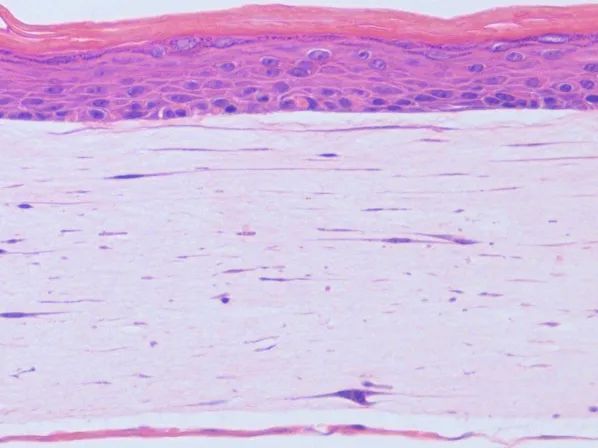

在肿瘤相关领域,赛箔与合作者共同研发基于生物3D打印技术构建的肿瘤微组织(PDT),涵盖十余个癌种,包括高发肿瘤、难治肿瘤、妇科肿瘤和儿童肿瘤,培养成功率超过了90%。通过近千例样本研究,证实PDT与患者组织具有高度一致的分子特征和药物敏感性,1-2周即可获得准确的药敏检测结果,为治疗赢取宝贵时间,并且可为新药研发企业提供药效评价、入组标准建立、适应症筛选等服务。在再生相关领域,赛箔已建立多种3D组织工程皮肤,包括表皮模型、全层皮肤模型、黑素皮肤模型等,并相应开发多种体外功效测试方法。

全层皮肤模型